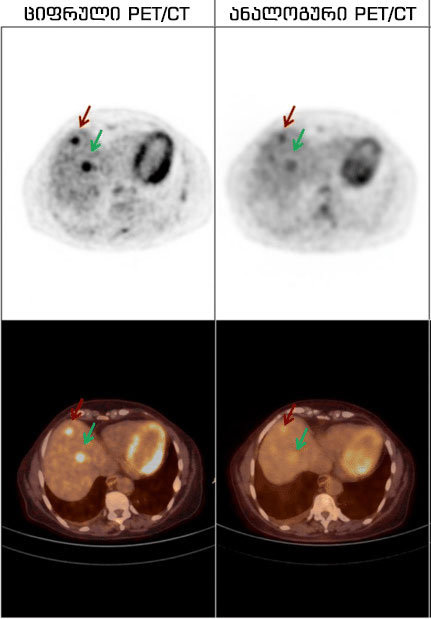

პეტ/კტ ბირთვული მედიცინის ფუნქციონალური დიაგნოსტირების მეთოდია, ჰიბრიდული კვლევაა, რომელიც აერთიანებს პოზიტრონულ-ემისიურ და კომპიუტერულ ტომოგრაფიას. ამ მონაცემების შეჯამებით კი, სიმსივნის ზუსტი მდებარეობა და წარმონაქმნის მეტაბოლიზმი ვლინდება. Philips Vereos digital PET/CT აპარატმა გლობალურ ბაზარზე აღიარება გამოჩენისთანავე მოიპოვა. იგი მსოფლიოში პირველი და ერთადერთი სრულად ციფრული სკანერია. სხვა ანალოგურ აპარატებთან შედარებით კი, ციფრული PET/CT:

· ავლენს ისეთი უმცირესი ზომის სიმსივნურ კერებსაც კი, რომლებიც 2-3 მმ-ს არ აღემატება და ვერ დადგინდებოდა „ანალოგური“ , ანუ ძველი თაობის პეტ აპარატის საშუალებით;

ძველი თაობის , „ანალოგური“ დანადგარებისგან განსხვავებით, მას შეუძლია მილიმეტრული სიზუსტით, ადამიანის სხეულის ნებისმიერ წერტილში არსებული ისეთი მცირე ზომის კიბოს უჯრედისა თუ გავრცელებული მეტასტაზების დანახვა და ზუსტი მდებარეობის განსაზღვრა, რომლებიც არ ჩანს კომპიუტერული ტომოგრაფიის, მაგნიტურ-რეზონანსული და სხვა რადიოლოგიური გამოკვლევების დროს. თავად, კომპანია Philips-ის შეფასებით, ეს არის აპარატი, რომლის გამჭრიახ თვალსაც მილიმეტრული ზომის წარმონაქმნიც კი არ გამოეპარება! ასევე, აღსანიშნავია, რომ პეტ/კტ კვლევა, ონკოლოგიურ შემთხვევათა 36%-ში, მკურნალობის ტაქტიკას ცვლის!